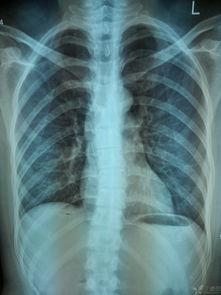

首先,让我们来认识一下脊柱的基本构成。脊柱由33块椎骨组成,分为颈椎、胸椎、腰椎、骶椎和尾椎五个部分。这些椎骨之间通过椎间盘连接,椎间盘就像弹簧一样,缓冲了脊柱在运动过程中的震动。

胸椎位于颈椎下方,共有12块椎骨。它们与肋骨相连,构成了胸廓,保护着心脏和肺部等重要器官。胸椎的椎间盘较厚,稳定性较好。视频讲解中会详细展示胸椎的结构,以及如何通过锻炼来增强胸椎的稳定性。